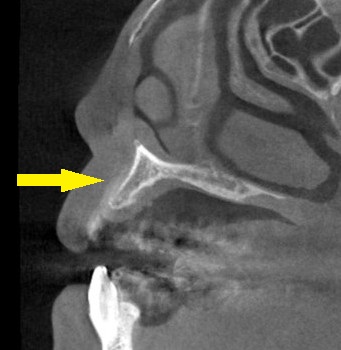

CTを撮影してみると、確かに骨が薄く、通常のインプラント埋入は無理だと判断しました。

下の写真が、手術前後のCTです。